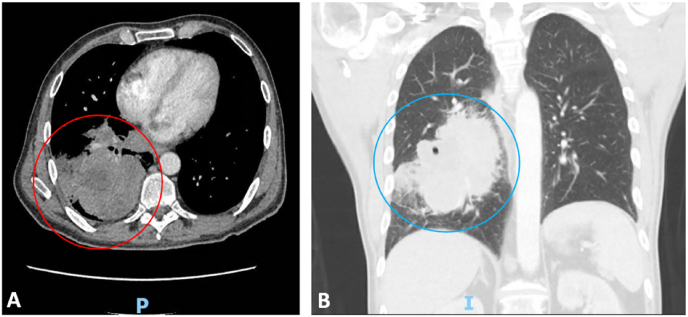

Fig. 3.

A-B:

A. 8.9 cm necrotic right infrahillar lower lung mass (red circle). P for posterior.

B. Coronal view of mass (blue circle) with associated pulmonary embolism in distal right main pulmonary artery with extension into the right upper and lower lobe segmental artery branches. I for inferior. (For interpretation of the references to colour in this figure legend, the reader is referred to the Web version of this article.)